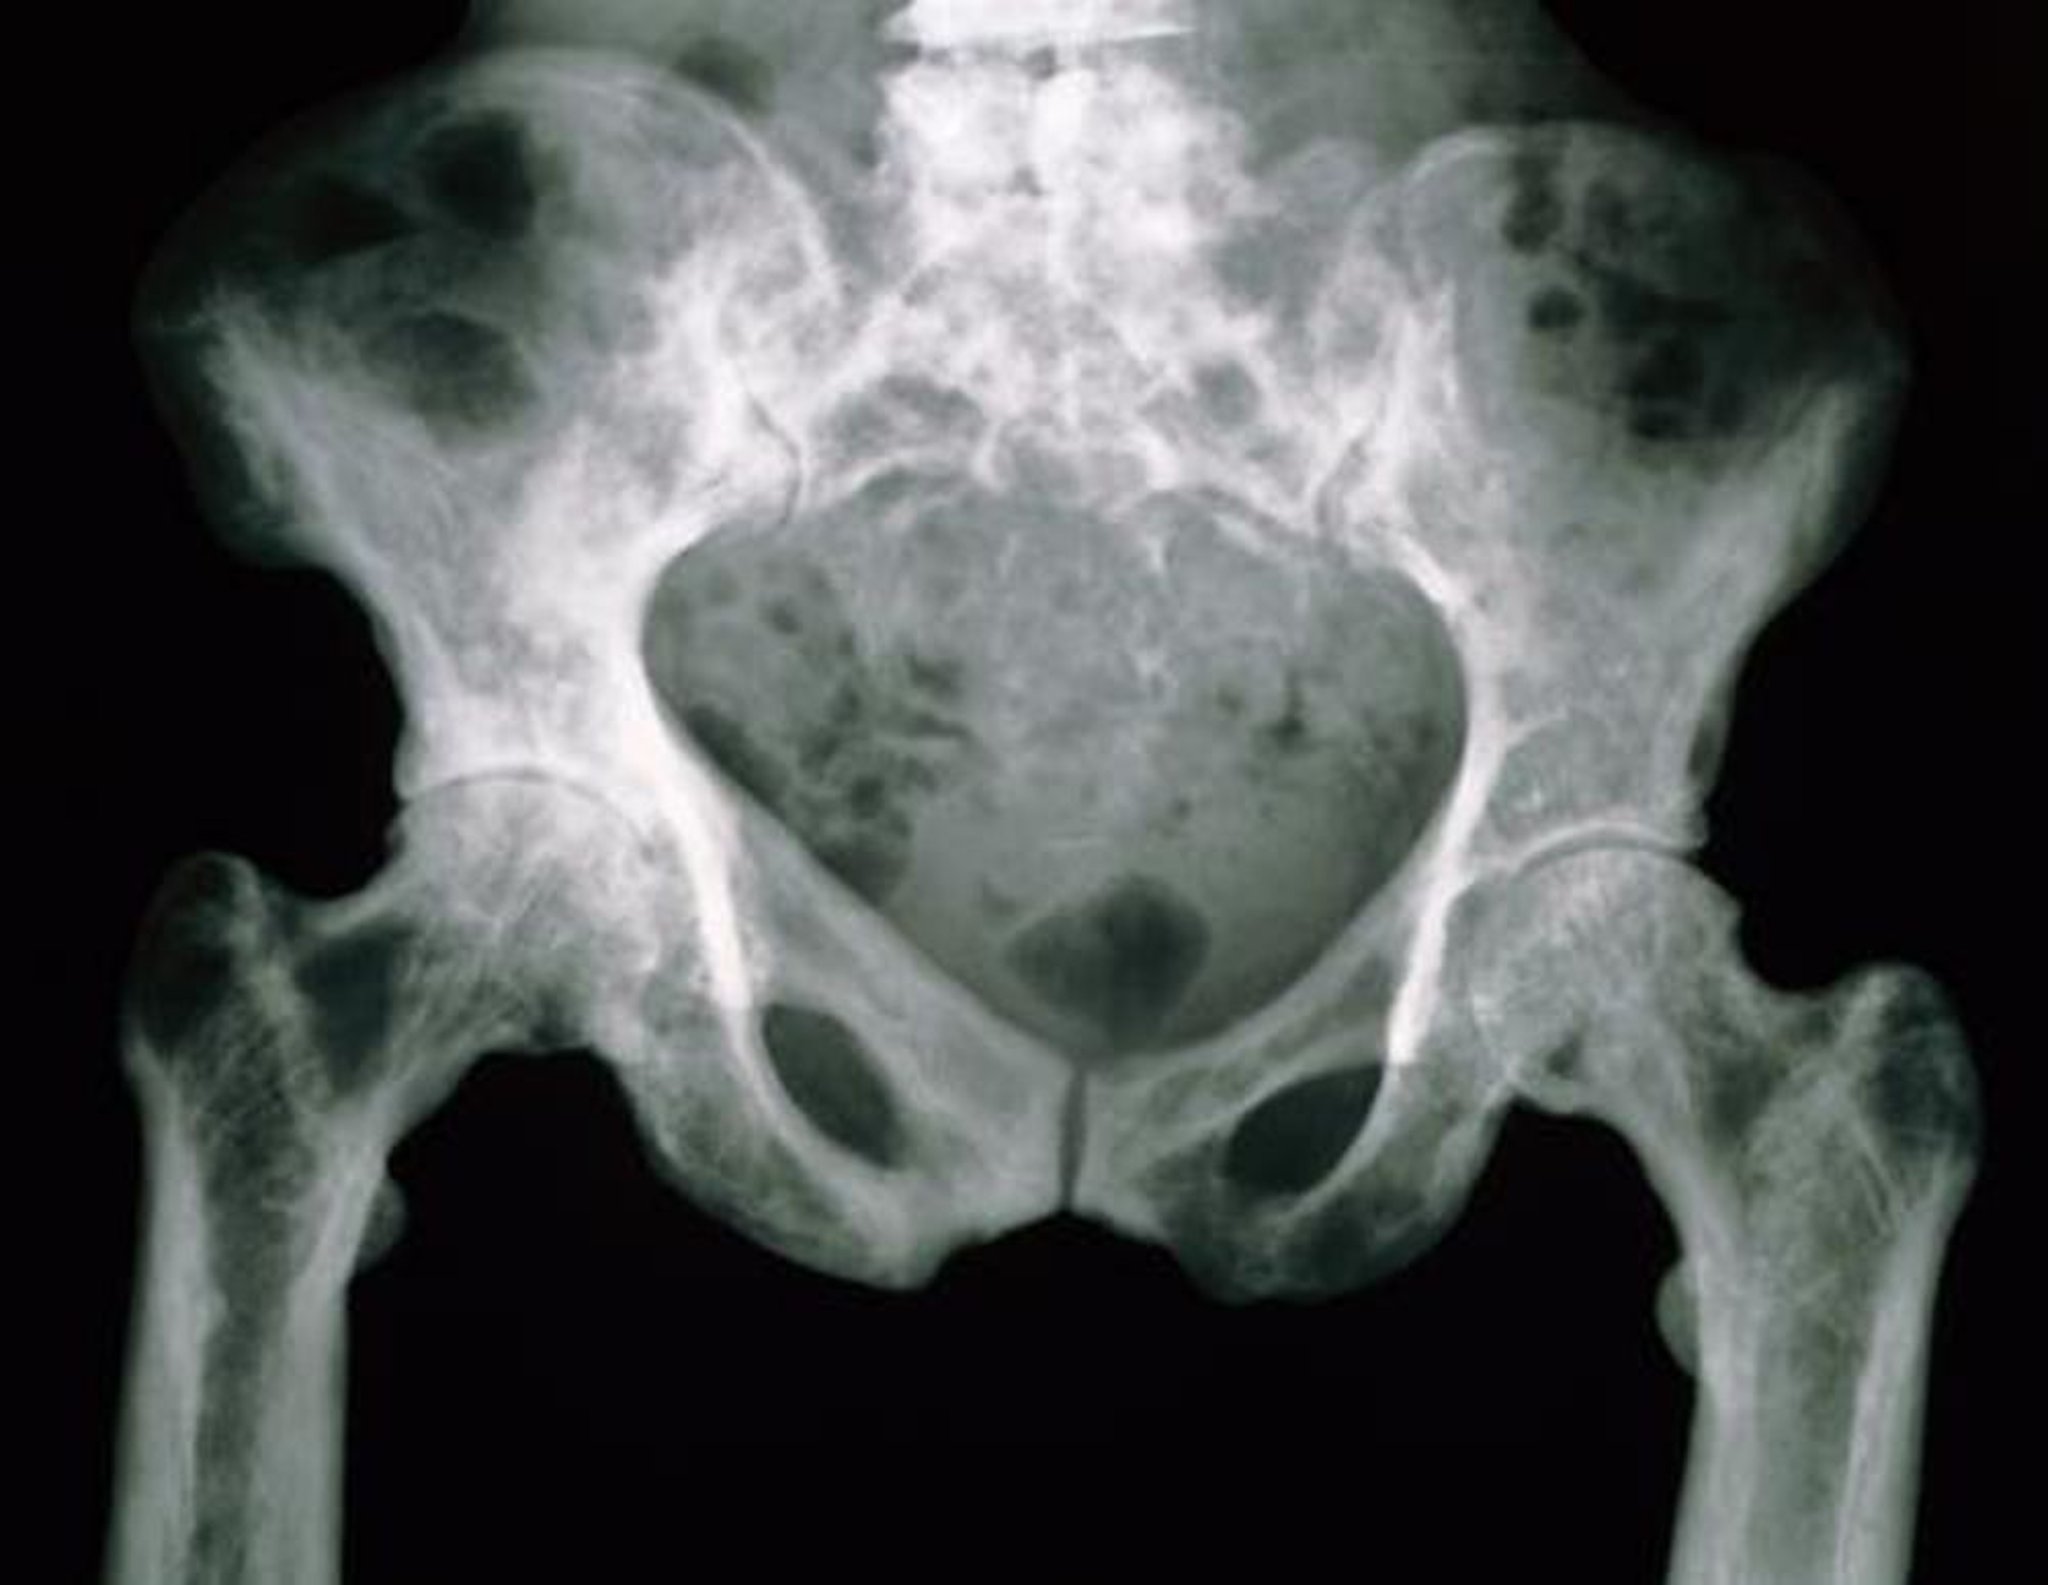

パジェット病における骨盤のX線

このX線像の骨盤骨は,多孔性の増加による斑状の外観を呈している。